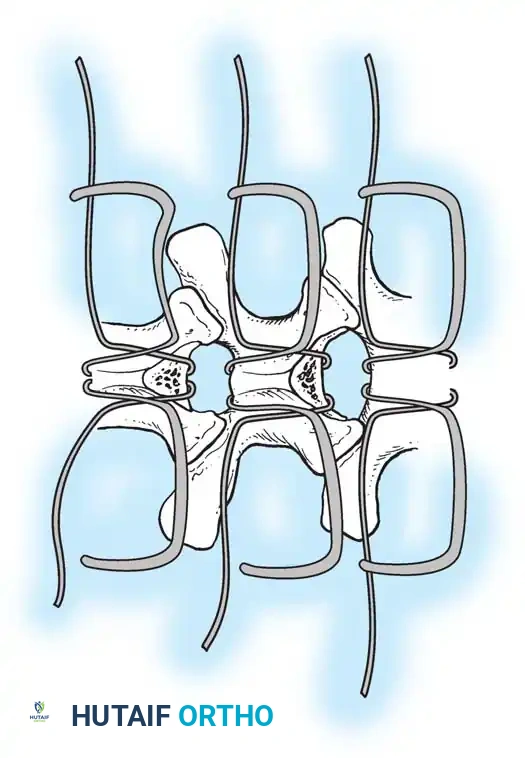

The Moe Technique (Thoracic Spine)

The Moe technique is a highly effective method for achieving intra-articular arthrodesis in the coronally oriented thoracic facet joints.

Fig. 38-26: The Moe technique of thoracic facet fusion, demonstrating the creation of hinged bone flaps.

- Expose the spine fully to the tips of the transverse processes.

- Using a sharp osteotome or Cobb gouge, begin a cut over the cephalad articular process at the base of the lamina.

- Carry this cut along the transverse process almost to its tip. Bend this cortical fragment laterally so it lies between the transverse processes, ideally leaving it hinged on its lateral periosteal attachment to preserve local vascularity.

- Thoroughly denude all articular cartilage from the superior articular process using a sharp curet.

- Make a secondary cut in the superior articular facet, working medially to laterally, producing another hinged fragment.

- Pack the resulting intra-articular defect tightly with cancellous bone graft.